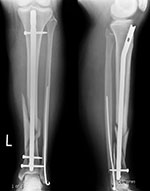

Intramedullary tibial nail and fibula Rush rod

Right tibia fracture dynamization

Right tibia dynamization - before

Right tibia dynamization - after

43 year-old man with complex, healing right tibia and fibular fractures. There is an intramedullary rod (nail) in the right tibia. Four locking screws are present proximally and two distally. After dynamization the distal locking screws have been removed.